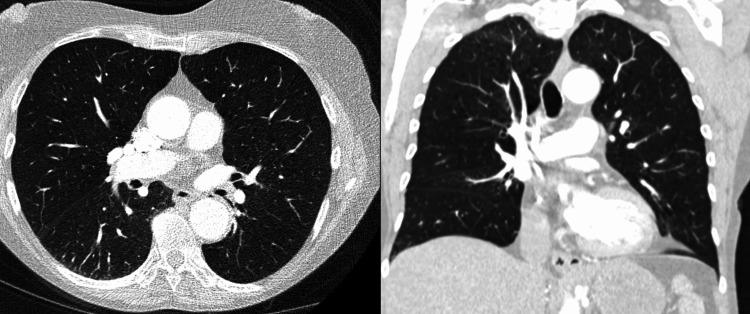

Babesiosis can present with a wide range of clinical manifestations, from asymptomatic infection to severe, life-threatening illness. We report the case of a 74-year-old woman with severe babesiosis complicated by Takotsubo cardiomyopathy. She presented with fever, chills, fatigue, and shortness of breath two weeks after a tick bite of unknown attachment duration. Initial testing for tick-borne illnesses, including , , , and , was negative. As her condition progressed, she developed hemolytic anemia, and a repeat peripheral blood smear revealed 4.5% parasitemia, confirming severe babesiosis. Despite treatment with atovaquone and azithromycin, her clinical status deteriorated, necessitating exchange transfusion, mechanical ventilation for respiratory failure, and hemodynamic support with inotropes and vasopressors for refractory cardiogenic shock. Echocardiography confirmed Takotsubo cardiomyopathy, which resolved with appropriate treatment. This case underscores the diagnostic complexity and potential severity of babesiosis, highlighting the importance of maintaining a high index of suspicion and initiating prompt therapy to prevent serious complications.

巴贝斯虫病可表现出广泛的临床表现,从无症状感染到严重的、危及生命的疾病。我们报告一例74岁女性严重巴贝斯虫病并发应激性心肌病的病例。她在被蜱叮咬(叮咬持续时间不明)两周后出现发热、寒战、疲劳和呼吸急促。对包括[此处原文缺失具体疾病名称]、[此处原文缺失具体疾病名称]、[此处原文缺失具体疾病名称]和[此处原文缺失具体疾病名称]在内的蜱传疾病进行的初步检测均为阴性。随着病情进展,她出现了溶血性贫血,再次进行外周血涂片检查发现疟原虫血症为4.5%,确诊为严重巴贝斯虫病。尽管使用了阿托伐醌和阿奇霉素进行治疗,但她的临床状况仍恶化,需要进行换血治疗、因呼吸衰竭进行机械通气,以及使用强心剂和血管加压药进行血流动力学支持以治疗难治性心源性休克。超声心动图证实为应激性心肌病,经适当治疗后病情缓解。该病例强调了巴贝斯虫病诊断的复杂性和潜在严重性,突出了保持高度怀疑指数并及时启动治疗以预防严重并发症的重要性。